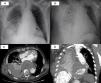

Varón de 69 años con endoprótesis vascular por aneurisma toracoabdominal, que acudió por síncope con posterior descenso del nivel de consciencia. Presentaba estabilidad hemodinámica, buena perfusión distal y discreta desaturación con taquipnea. La tomografía computarizada (TC) craneal, descartó sangrado y la radiografía de tórax (fig. 1A) reveló un aumento de densidad en la base pulmonar derecha. La analítica mostró leucocitosis con desviación izquierda y elevación de reactantes de fase aguda. Con diagnóstico de neumonía bacteriana, se inició tratamiento con levofloxacino. A las pocas horas, se recibió antigenuria positiva para Streptococcus pneumoniae. La evolución analítica fue desfavorable y ante la sospecha de sepsis con fallo multiorgánico se amplió antibioterapia. Posteriormente, el paciente presentó un deterioro respiratorio brusco, ausencia de pulsos radial y pedio izquierdos, y parada cardiorrespiratoria. Se realizaron maniobras de resucitación y reposición hemática por sospecha de sangrado por rotura aneurismática. La radiografía de tórax (fig. 1 B) reveló velamiento del hemitórax derecho y la angio-TC de aorta (fig. 1C-D) identificó una endofuga aneurismática con sangrado activo hacia espacio pleural con importante hemotórax derecho. No pudieron ofrecerse alternativas terapéuticas quirúrgicas, con el posterior fallecimiento del paciente.

A) Radiografía de tórax anteroposterior al ingreso: cardiomegalia, elongación aórtica con endoprótesis (flecha) y área de aumento de densidad en la base pulmonar derecha en probable relación con patología infecciosa. B) Radiografía de tórax anteroposterior tras empeoramiento clínico: importante derrame pleural con velamiento de hemitórax derecho (asterisco). C) TC torácica en plano axial. D) TC torácica en plano sagital: en aorta torácica descendente se objetiva endofuga que se extravasa como sangrado activo hacia cavidad pleural derecha produciendo importante hemotórax (flechas), que colapsa todo el lóbulo inferior derecho y el segmento posterior del lóbulo superior (fístula aortopleural).